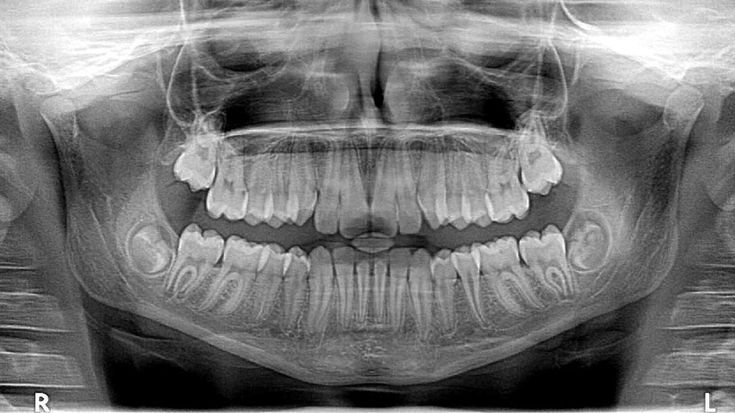

Панорамный снимок (ОПТГ) - это плоскостное изображение, где возможности доктора планировать адекватное лечение урезаны до минимума.

P.S. Ребёнку младше 8 лет обычно делают ОПТГ.